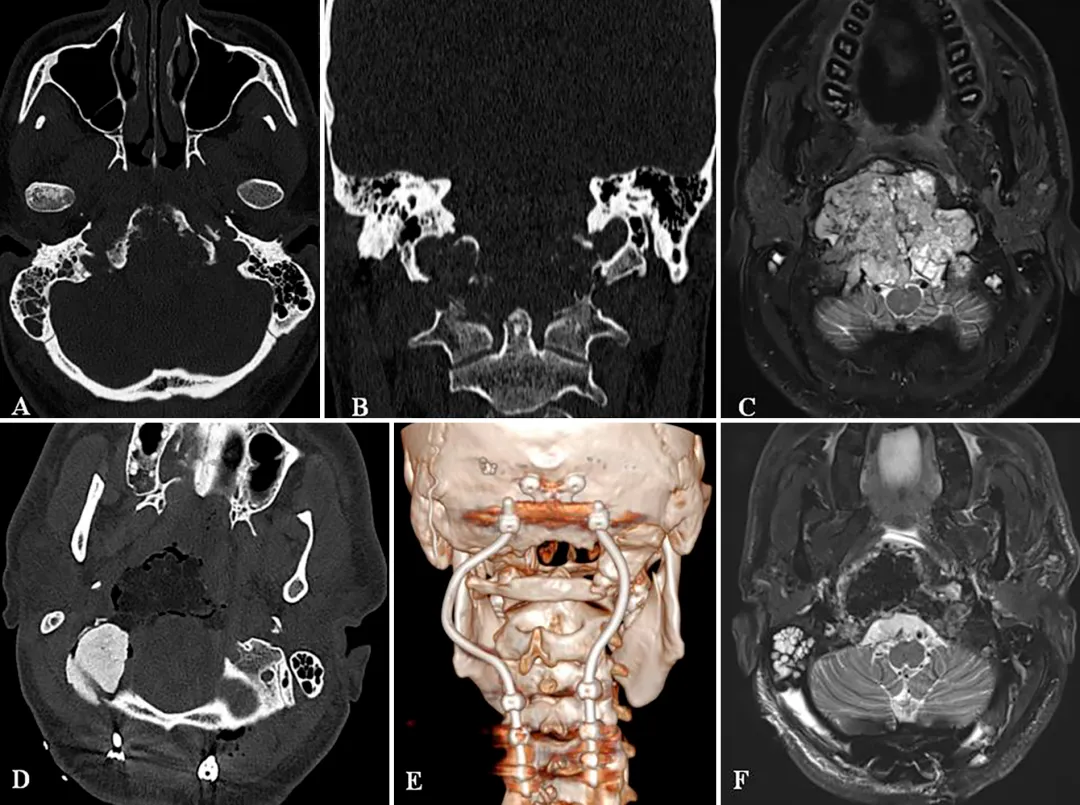

图A和图B:术前CT扫描显示颅颈交界区脊索瘤,侵犯斜坡-枕骨髁并呈溶骨性破坏。

图C:术前磁共振成像(MRI)显示肿瘤巨大,并向硬膜内脑实质浸润性生长。

图D:术后CT扫描显示PMMA材料进行的枕骨髁重建稳定性良好。

图E:术后三维CT重建显示C0-C3-C4-C5节段的枕颈融合稳定性良好,连接杆的弯曲设计有利于后续的质子束放射治疗。

图F:术后磁共振成像(MRI)显示肿瘤被完全切除,脑干及延髓的占位压迫已解除。